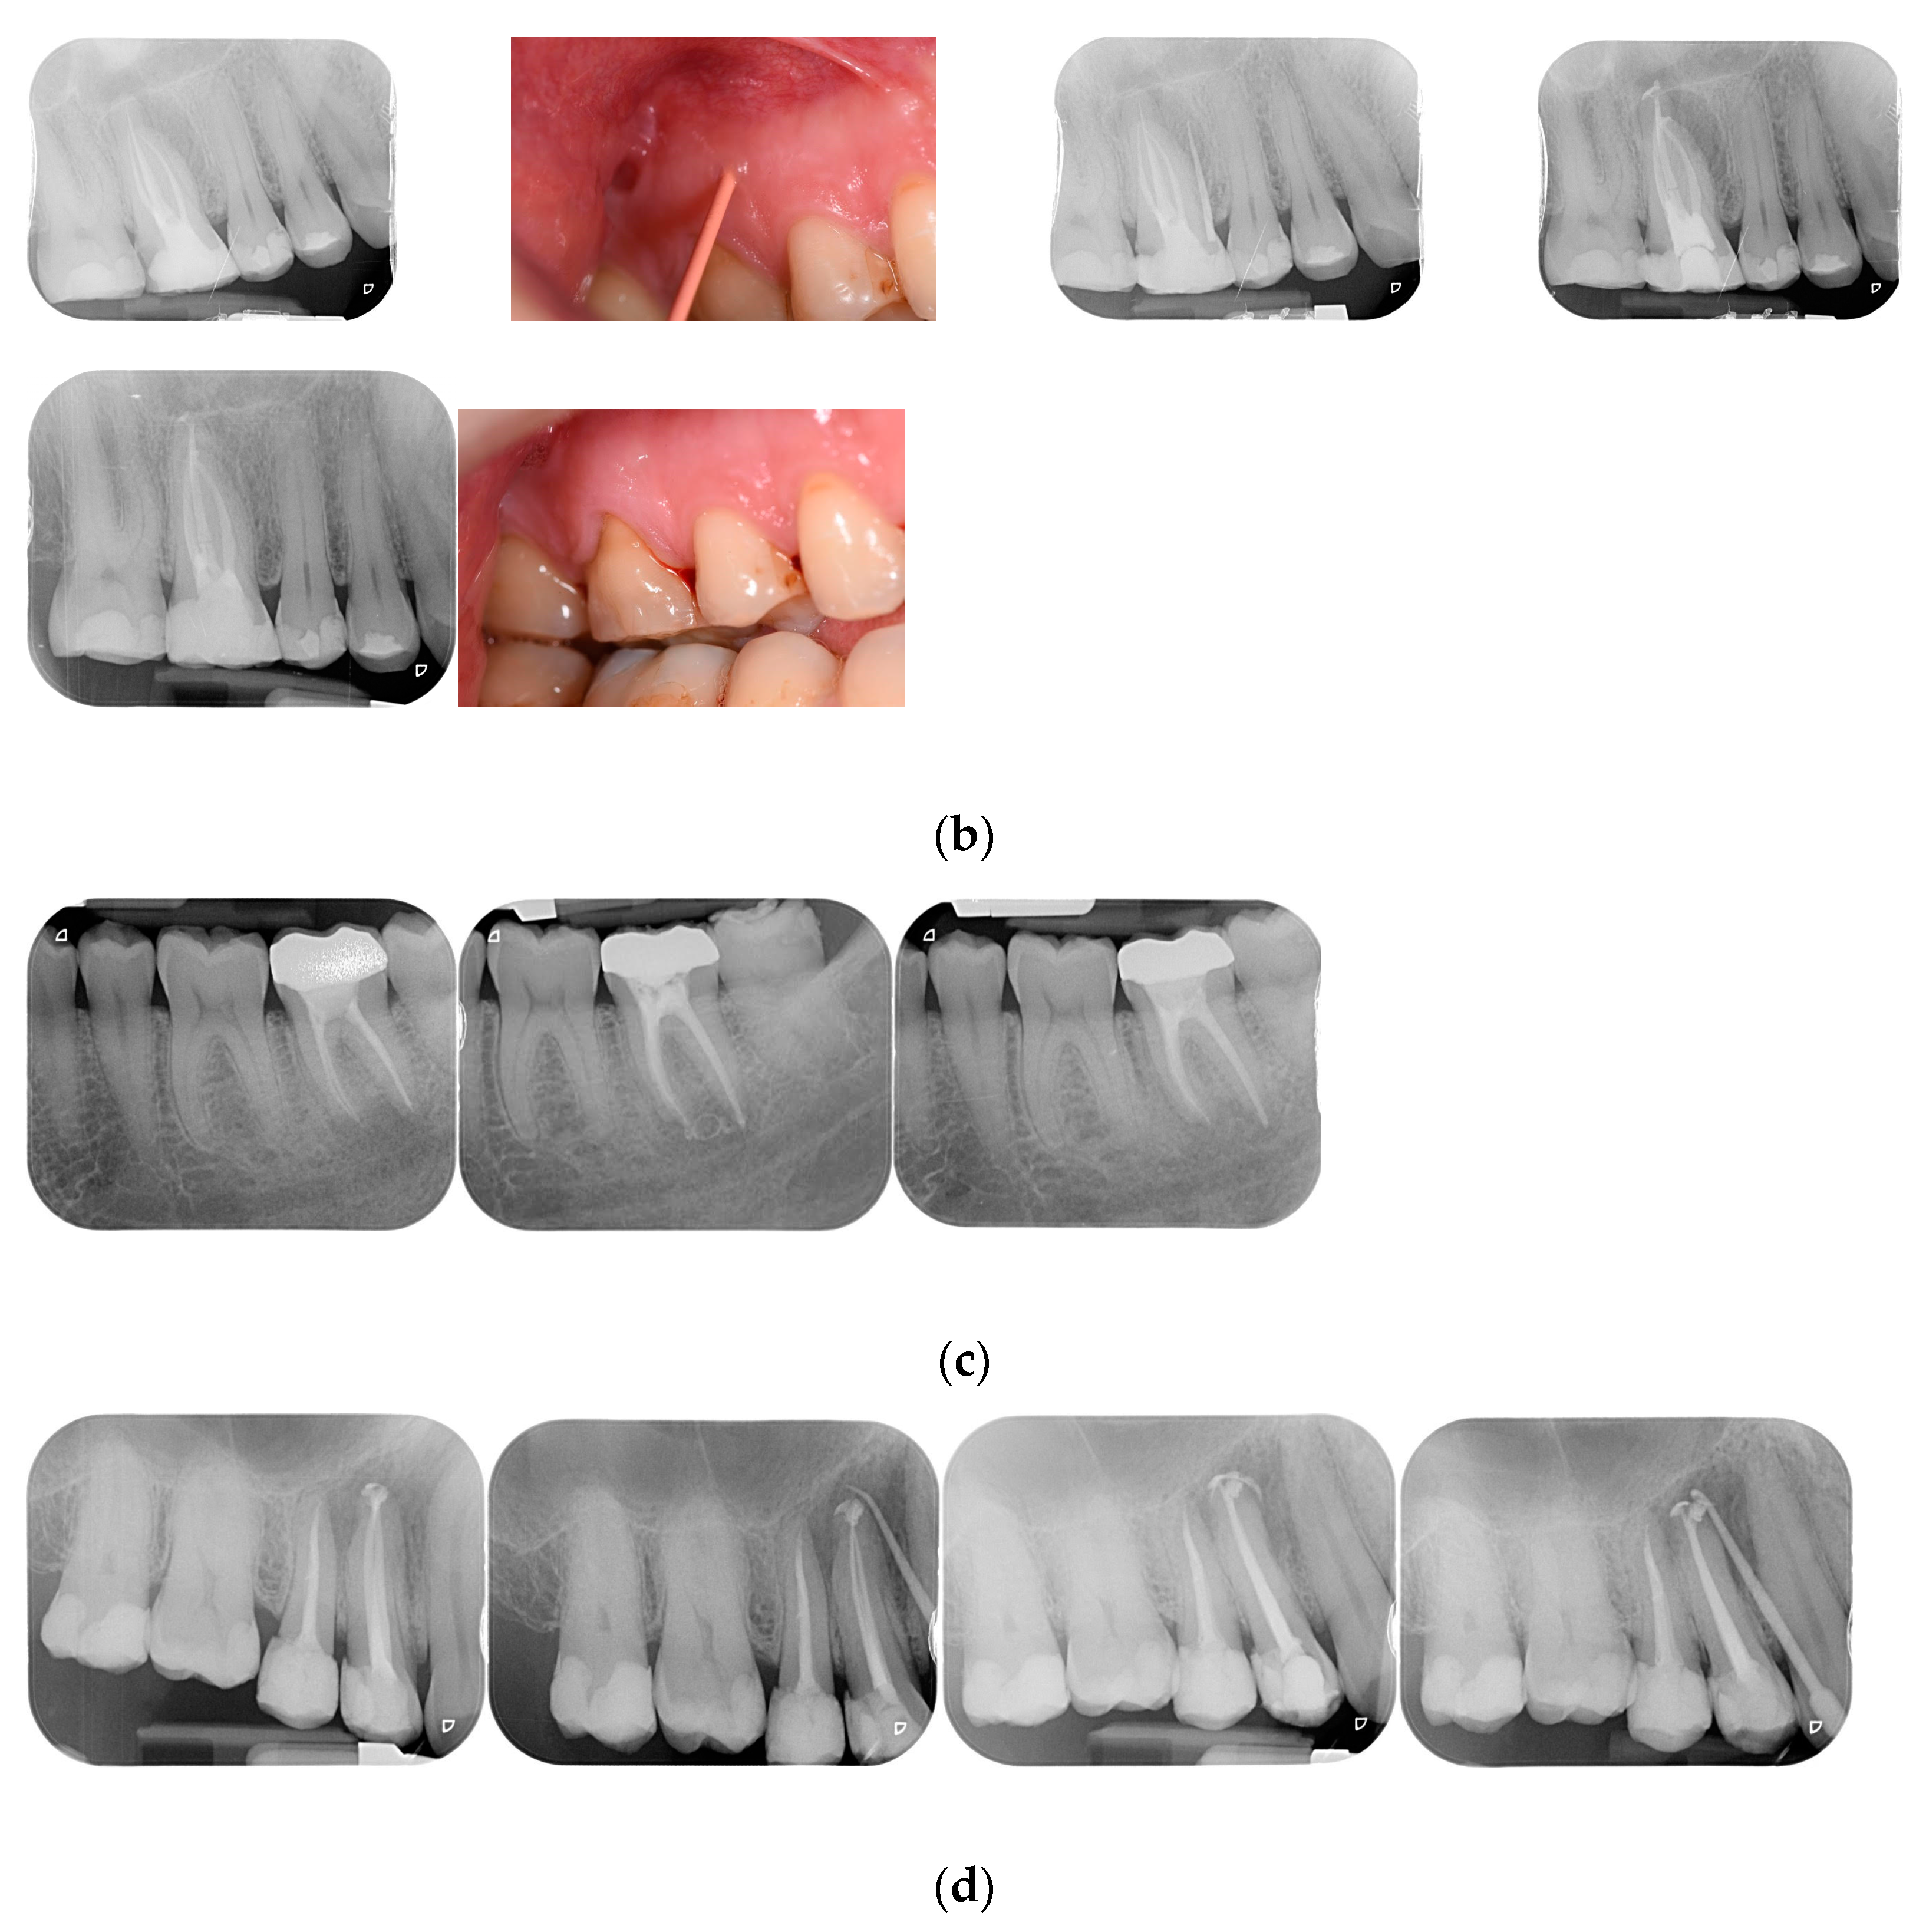

The clinical evaluation ‘success’ was referred to healed and healing categories and ‘failure’ to the not-healed teeth was classified as failure. Figure 1 show examples of each category. When a disagreement on the radiographic and/or clinical evaluation between the two evaluators was present, a discussion was made and a final consensus was reached. Examples of each outcome category are shown in Figure 1a–d.

Figure 1.

(a) Healed lower incisor at 12 months recall. (b) Healed upper first molar at 18 months recall. (c) A lower second molar in healing process after 6 months. (d) Not healed first upper bicuspid at 8 months recall.